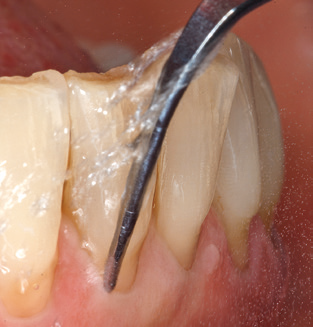

Die gute Ausleuchtung des Arbeitsfeldes stellt eine wesentliche Erleichterung dar. Bei dem von den Autoren genutzten System ist dies gelungen, indem ein 5facher LEDRing in das Handstück integriert wurde. Natürlich werden für dieses System unterschiedliche Arbeitsspitzen für die jeweiligen Indikationsbereiche angeboten. Eine gerade, universell einsetzbare Spitze ist das Basisinstrument zur maschinellen Instrumentierung natürlicher Zähne (Abb. 5a und b). Für schwer zugängliche Bereiche im Seitenzahnbereich werden gebogene Spitzen angeboten, die auch einen Zugang zu freiliegenden Furkationen ermöglichen (Abb. 6).

Im Rahmen des gesammelten Patientenfeedbacks stellte sich heraus, dass das System darüber hinaus auch zwei Punkte bietet, die den Patientenkomfort steigern. Dies ist zum einem das Vorwärmen der Spülflüssigkeit, die auch beim Reinigen empfindlicher Zahnoberflächen eine Reizung vermeidet, und der sogenannte Smooth Mode des Systems. Bei diesem Modus verringert sich die Leistung des Systems, je stärker die Spitze an den Zahn gedrückt wird. Diese beiden Aspekte führen dazu, dass die Patienten die Behandlung angenehmer finden als mit früher verwendeten Ultraschallsystemen.